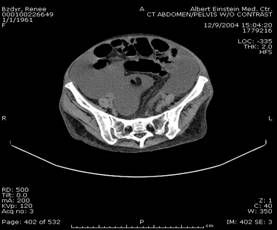

Normal epiploic appendages